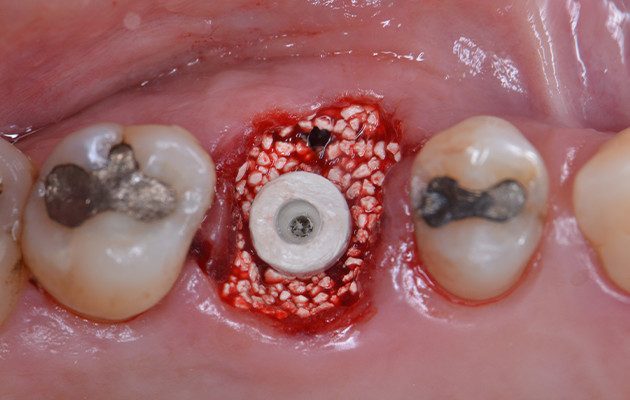

10 | Preenchimento do alvéolo fresco com biomaterial substituto ósseo de origem sintética. Destaque para o Tapa Implante colocado para prevenir a entrada do biomaterial dentro do implante

11 | Cicatrizador Multifuncional Arcsys posicionado sobre o implante.

12 | Resina composta fluida unida ao Cicatrizador se estendo até as margens do tecido mole para manter o contorno tecidual durante o período de osseointegração do Implante.